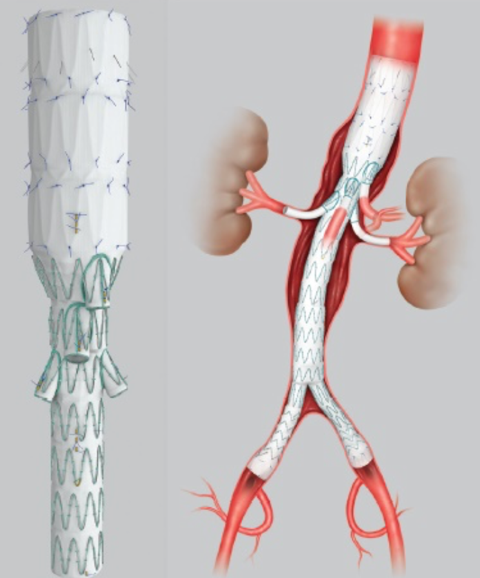

2022-11-07Lekarze Kliniki Chirurgii Naczyniowej, Ogólnej i Angiologii naszego szpitala dokonali pierwszego w kraju, całkowicie przezskórnego wszczepienia modyfikowanego stent-graftu. Była to operacja ratująca życie, a pomocna przy tym - technika druku 3D.

Dostępy całkowicie przezskórne (bez cięcia skóry) wykonuje tylko kilka ośrodków w Polsce i jest to metoda coraz częściej preferowana, ale głównie do mniej skomplikowanych przypadków. Tym razem do szpitala na Pomorzanach trafił 75-letni pacjent z objawowym tętniakiem okołotrzewnym (aorty piersiowo-brzusznej) - bolesnym, grożącym pęknięciem, a zatem stanowiącym zagrożenie życia. Dodatkowo chory nie miał szans na skorzystanie ze standardowego stent-graftu branchowego (z doszywanymi „rękawkami” na naczynia) czy fenestrowanego (z wyciętymi „okienkami” na naczynia) zamawianego u producenta z powodu występujących u niego dodatkowych naczyń, odchodzących od aorty (osobne ujście tętnicy wątrobowej). Nie mógł też czekać na wyprodukowanie stent-graftu szytego dla niego na miarę, bo trwałoby to 8-12 tygodni, a bolesność tętnika świadczyła, że rychło pęknie. Groziło to śmiercią pacjenta.

Leczenie stent-graftami modyfikowanymi jest w domeną naszych lekarzy Kliniki Chirurgii Naczyniowej, Ogólnej i Angiologii, którzy wypracowali wysokiej jakości standard postępowania w użyciu tej metody. Wykorzystując model aorty danego pacjenta, wydrukowany techniką 3D, modyfikują własnoręcznie, już na sali operacyjnej standardowe stent-grafty i dopasowują je indywidualnie do anatomii operowanego pacjenta. Po co? Bo mimo ogólnej takiej samej budowy każdego z nas, układ naczyń krwionośnych, ich budowa, odległości między poszczególnymi naczyniami różnią się u każdego człowieka. Dlatego dla efektywności działania wszczepianego, standardowego stent-graftu – proteza ta powinna być dopasowana do budowy chorego. Chirurdzy naczyniowi USK-2 są jedynym zespołem w Polsce, który tego typu zabiegi wykonuje rutynowo, również w przypadkach nagłych. Jednak taki sposób leczenia, jak i wszelkie inne zaawansowane procedury aortalne, wymaga licznych, często trudnych dostępów naczyniowych (np. nacięć w pachwinach, rękach i klatce piersiowej) – tj. cięć i operowania „na otwarto”. Dla chirurga taka operacja jest łatwiejsza, bo pole operacyjne jest widoczne jak na dłoni. Ale dla pacjenta dochodzenia do formy po takiej operacji jest długotrwałe, bolesne i mało komfortowe. Dlatego użycie przez szczecińskich lekarzy wyłącznie dostępu przezskórnego (bez cięcia) w leczeniu tętnika jest dużym krokiem na przód w chirurgii naczyniowej, a fakt, że to pierwszy tego typu zabieg w Polsce to ogromny sukces naszych „naczyniowców” i świadczy o ich doskonałej technice operowania.

„Modyfikacja stent-grafu naszą, ‘szczecińską metodą’ pozwoliła na pokonanie technicznych trudności, dostosowanie protezy do chorego i wykonanie zabiegu „od ręki”. Zastosowaliśmy modyfikację stent-graftu z okienkami na cztery naczynia trzewne - mówi dr hab. n. med. Arkadiusz Kazimierczak, który wraz z dr. n. med. Pawłem Rynio operował mężczyznę. „Wykonanie przezskórne - dwa dostępy do tętnicy podobojczykowej na klatce piersiowej i obu udowych w pachwinach, zamiast jak dotychczas czterech - pozwoliło na zminimalizowanie urazu operacyjnego tak, że chory był w pełni uruchomiony już w pierwszej dobie po zabiegu i zapytał o termin wypisu ze szpitala – dodaje dr Paweł Rynio. Operacja odbyła się 20 września.

Obaj lekarze są członkami szczecińskiego Aortic Teamu, zespołu chirurgów naczyniowych i kardiochirurgów stosujących nowatorskie metody leczenia w przypadku tętniaków. Zespół planuje rozszerzenie wskazań do zabiegów całkowicie przezskórnych w leczeniu patologii łuku aorty. Pierwsze próby z ograniczeniem urazu operacyjnego w tym zakresie zostały już podjęte w przypadku innej operowanej chorej. Tym razem zastosowano dwa małe cięcia przy wymianie całego łuku aorty, zamiast jak dotychczas pięciu. Pacjentka również jest w dobrym stanie.

Tłumacząc obrazowo - tętniakiem aorty nazywany nadmierne (o ponad 50%) poszerzenie aorty, która jest największą tętnicą w ciele człowieka. Może ono występować na każdym jej odcinku, ale najczęściej występuje w części brzusznej. Przyczyną ich powstania jest odkładanie się blaszek miażdżycowych, nadciśnienie tętnicze, nadmierny, gwałtowny wysiłek czy uraz, czasem także wrodzone nieprawidłowości w budowie naczynia. Ryzyko wystąpienie tętniaka aorty brzusznej wzrasta z wiekiem i jest szczególnie wysokie u mężczyzn około 65. roku życia. Szczególnie niebezpieczne są tętniaki bezobjawowe, które w każdej chwili mogą grozić pęknięciem i prowadzić do zgonu chorego.